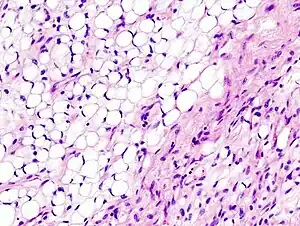

| Histopathologic image of myxoid liposarcoma arising in the deep soft tissue of the thigh. H & E stain. | |

Micrograph of myxoid liposarcoma. H&E stain